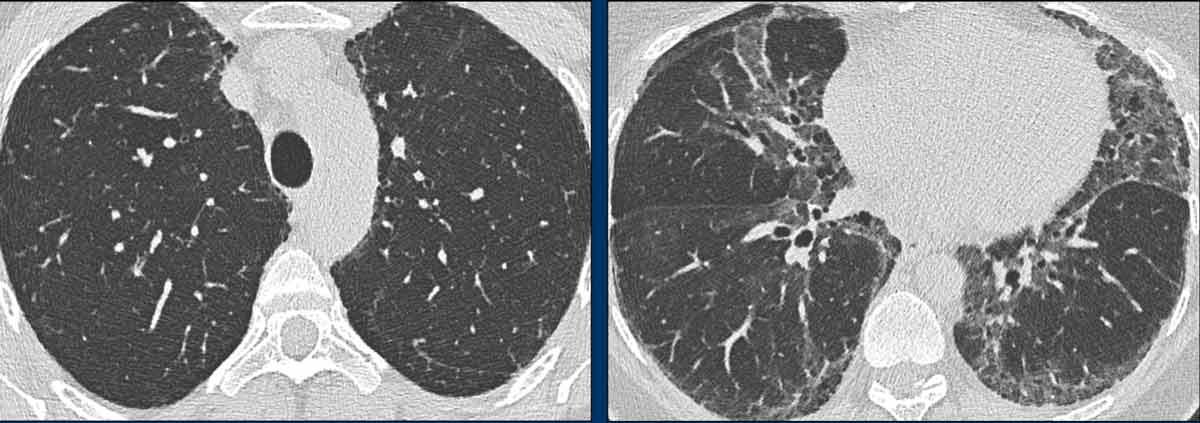

Hình ảnh

- Các nang có hình dạng kỳ dị ở một bệnh nhân nam mắc LCH.

- Trường hợp nặng của LCH giai đoạn tiến triển, hình ảnh tương tự khí phế thũng. Ở một bệnh nhân nữ không có tiền sử hút thuốc, đây cũng có thể là trường hợp LAM (bệnh cơ trơn bạch huyết) nặng.

- Nhiều nốt, một số đang tạo hang, với phân bố ưu thế ở vùng phổi trên (khác với di căn), và hoàn toàn không tổn thương các ngách màng phổi.

- Sự kết hợp giữa các nang kỳ dị, các nốt và các nốt đang tạo hang với phân bố ưu thế ở vùng phổi trên.

Đây là hình ảnh của một bệnh nhân nam 66 tuổi, có tiền sử hút thuốc lá và đến khám vì triệu chứng khó thở.

Hãy phân tích hình ảnh.

Đâu là dấu hiệu đặc trưng nhất?

Chẩn đoán có khả năng nhất là gì?

Nhận xét hình ảnh

Ghi nhận nhiều nang.

Một số có hình dạng bất thường và một số có dấu hiệu “cheerio” (hình vòng tròn) do hiện tượng tạo hang bên trong nốt (mũi tên trắng).

Ngoài ra còn ghi nhận một số nốt (mũi tên đen).

Bình luận

Sự kết hợp của các dấu hiệu này trên một bệnh nhân hút thuốc lá là điển hình cho chẩn đoán LCH.

Tiếp tục…

Trên tái tạo mặt phẳng coronal, có thể thấy rõ ràng rằng các nang chủ yếu tập trung ở thùy trên và thùy giữa, trong khi vùng đáy phổi được bảo tồn.

Đặc biệt khi LCH còn ở giai đoạn nốt, sự phân bố này có thể là dấu hiệu hữu ích trong việc phân biệt với di căn phổi, vốn có xu hướng ưu thế ở thùy dưới.

Đây là một trường hợp tương tự.

Lưu ý rằng các nang chủ yếu tập trung ở thùy trên và thùy giữa.

Các ngách màng phổi được bảo tồn.

Các nang đã gây ra tràn khí màng phổi.

Chẩn đoán phân biệt LCH 1

Đây là ví dụ về các nốt và nốt tạo hang có tổn thương các ngách màng phổi.

Đây là các tổn thương di căn từ ung thư biểu mô tế bào chuyển tiếp.

Sự phân bố tổn thương là yếu tố hữu ích trong việc phân biệt di căn phổi và LCH.

Một số di căn phổi có hiện tượng tạo hang nguyên phát, trong khi một số khác tạo hang do kết quả của điều trị.

Chẩn đoán phân biệt LCH 2

Đây là hình ảnh của hai bệnh nhân khác nhau.

Mặc dù thoạt nhìn hai hình ảnh này trông có vẻ tương tự nhau, có thể nhận thấy rằng ở bên trái là các nang thực sự có thành trong một bệnh nhân LCH giai đoạn tiến triển, trong khi ở bên phải một số tổn thương có vẻ có thành nhưng phần lớn thì không.

Đây là hình ảnh khí phế thũng trung tiểu thùy.